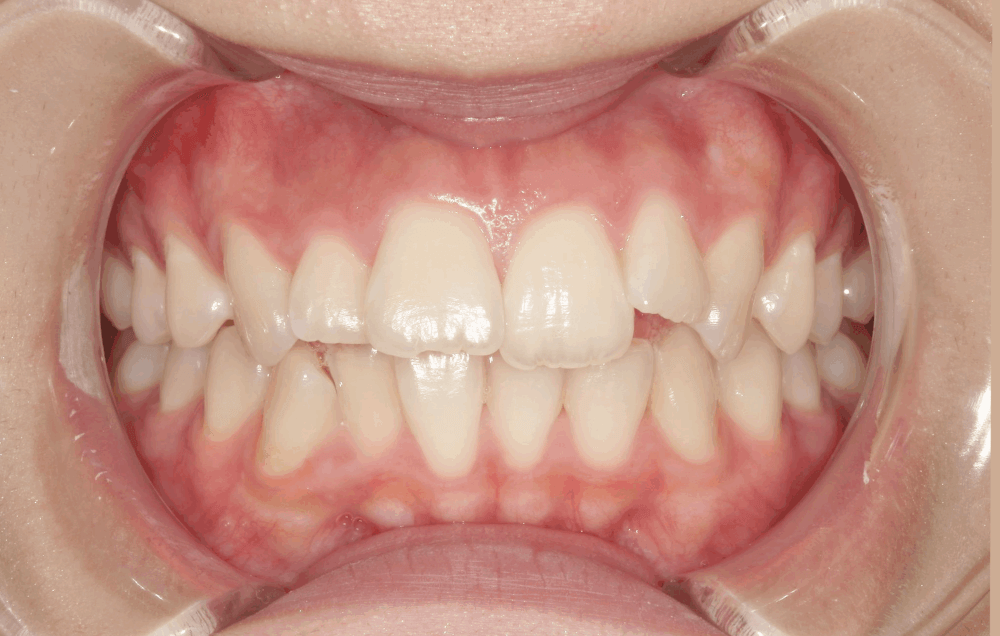

治療前の状態

<初診時>

上の前歯の横の歯(前から2番目)が前方に飛び出しており、全体的にガタつき(叢生)が見られます。これは、歯の大きさに対してあごの幅がやや狭く、歯がきれいに並ぶスペースが足りないために起こります。

また、上下の前歯の中心(正中線)がわずかにずれており、奥歯のかみ合わせやあごの位置の影響がみられました。

上の前歯1本が前に出ており、いわゆる「出っ歯」の状態です。見た目の印象だけでなく、口を閉じにくい・前歯で噛みにくいなどの機能面への影響もありました。

横から見ると、Eライン(鼻先とあご先を結ぶ線)より内側に口元があります。しかし、口を閉じるときに力が入ることでリップラインが不自然になり、少しふくらんで見える状態でした。患者様自身もこの「口元の力み」を気にされており、原因は上顎前歯の突出(出っ歯)によるものでした。

こうしたタイプの口元は、見た目の問題だけでなく、「口が閉じにくい」「力を抜くと少し開いてしまう」といった機能面にも影響することがあります。